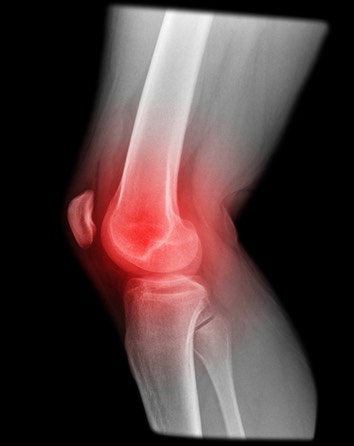

The Arthritic Knee

Arthritis causes a wearing out of the knee cartilage

Knee arthritis is a progressive wearing out of the normal articular cartliage that lines the moving surfaces of the knee. As the cartilage wears away it can become frayed and rough, and the thickness of the protective cartilage decreases. This wear and tear can be a slow and progressive process or can develop because of a prior injury. As the arthritic process progresses it can result in bone rubbing on bone, and become progressively more painful. The “environment” in an arthritic knee allows the “breaking down” (catabolic effect) process of the cartilage and meniscus to continue. The wear and tear cycle just continues until the knee is completely worn out.